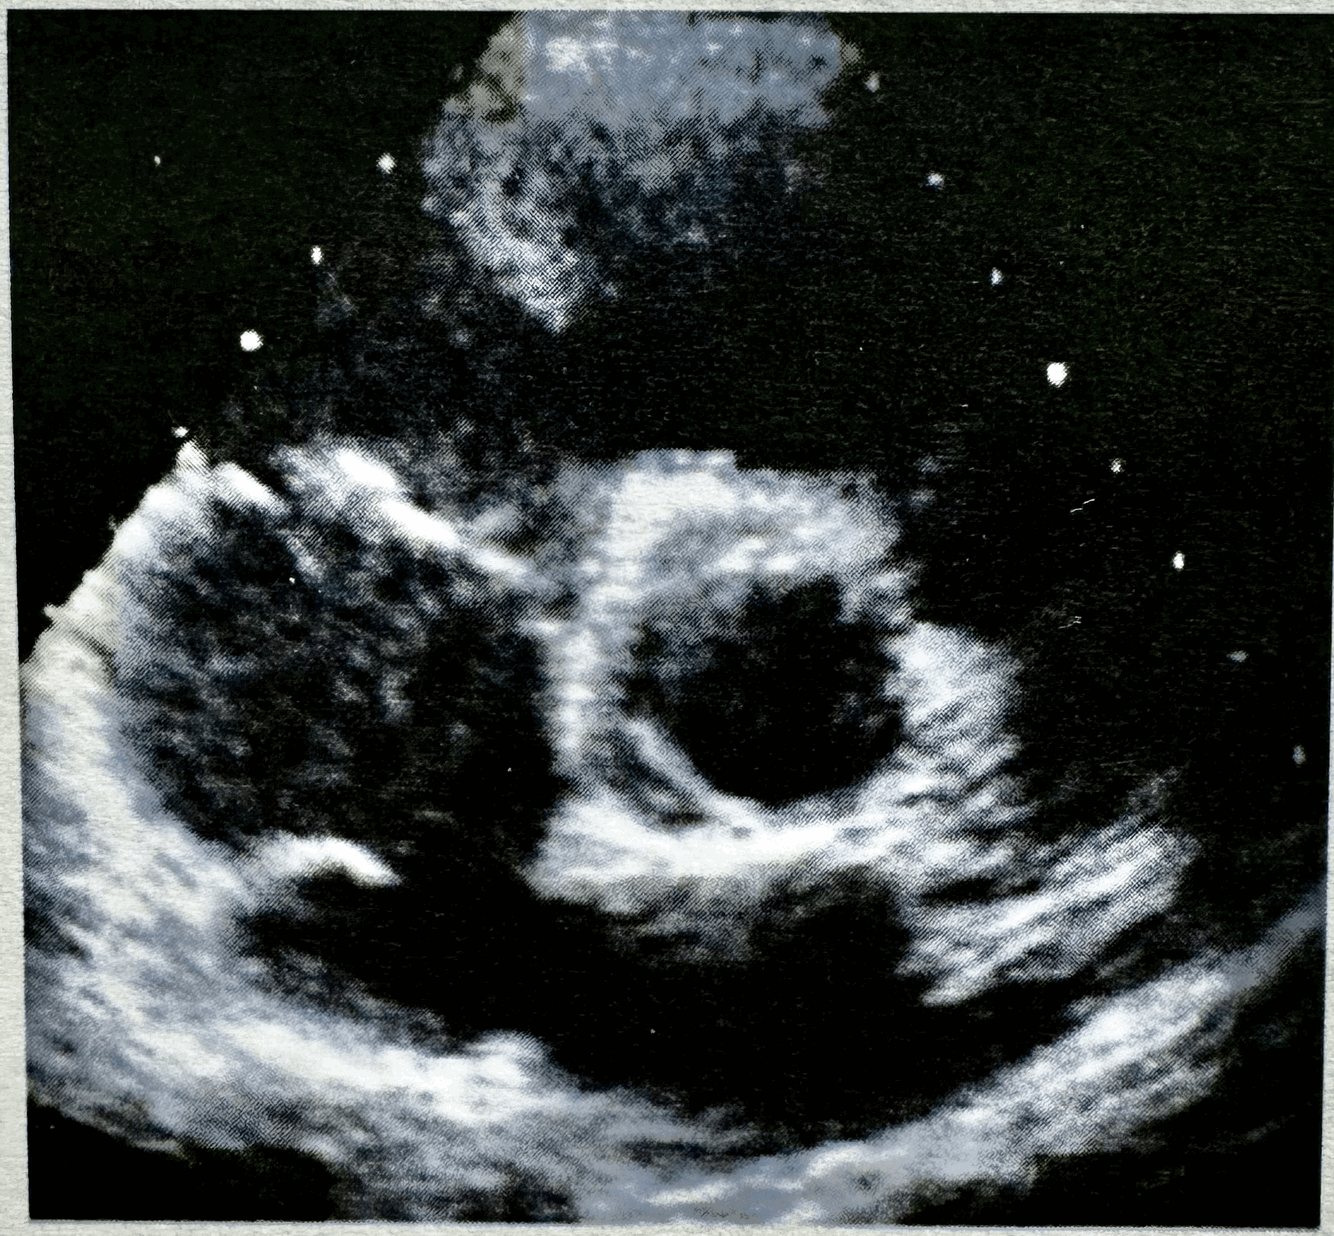

Q

What plane and is it diastole or systole?

A

PSAX, systole